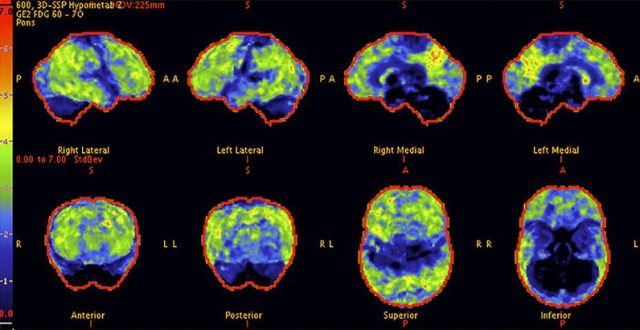

Above:The before PET scan of a 68-year-old woman with a 10-year history of cognitive difficulties shows prominent hypometabolism with a pattern suggestive of Alzheimer’s disease

Above:The after PET scan of the patient after treatment with inhibitor (RI). As the scan gradually approach that of a normal brain, the patient’s cognitive abilities improved dramatically.